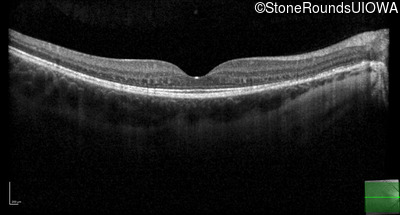

Optical Coherence Tomography - Right - 20/50 +2

Exemplar / OCT Stack